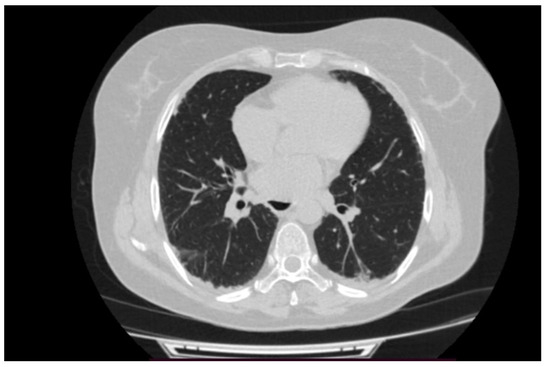

2. Case Presentation